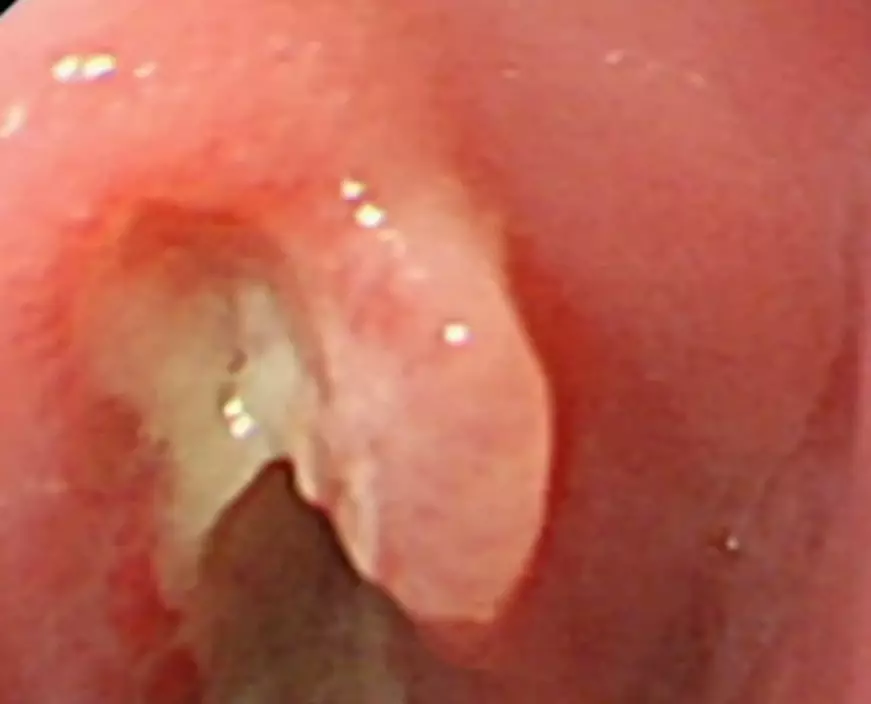

醫院消化科經過胃鏡手術,取出卡在寧寧食道的紐扣電池。不過,他的食道已被電池釋放的化學物質灼傷並出現穿孔。醫生表示,「經過全面問診,患兒誤吞電池的時長大致已有10小時左右,對食道已造成不可逆的損傷。電池取出後我們通過禁食、引流抑酸,空腸營養支持讓食道得以休整;大約兩週後造影發現灼傷的食道因瘢痕形成狹窄,導致吞咽困難。後續我們又多次進行食道擴張治療,盡可能恢復食道功能,目前孩子仍在治療中」。

醫生強調,紐扣電池一旦滯留食道猶如啟動「微型電烙鐵」,可在短時間內造成嚴重灼傷。若超過6小時,穿孔風險大增,部分患者甚至需要切除部分食道,或面臨長期進食困難。